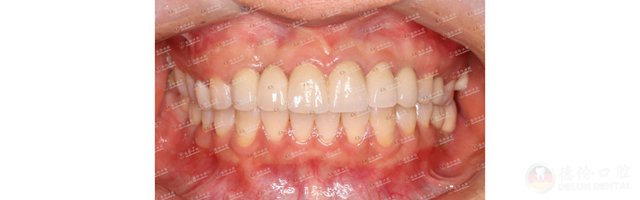

魏女士因牙齿不齐,笑起来不太自信,甚至不愿意笑,想一解烦恼的魏女士选择了德伦口腔东风总院正畸科副主任王苏静进行正畸治疗。嘴凸、牙不齐、薄龈型、且根形明显,王主任在详细检查过魏女士牙齿情况后为其设计了金属自锁的正畸方案,魏女士加入矫牙变美的道路。

魏女士看着自己的牙齿逐渐变得整齐好看,笑起来越来越自信了。回顾矫牙前的自己,笑容始终有一丝放不开,如今在王主任的正畸技术下牙齿逐渐变得整齐,自己的脸型也逐渐变美。

历经23个月,魏女士终于成功“毕业”!魏女士对王主任心怀感激,特意献上一面锦旗,虽然这只是一面简单的锦旗,但这面锦旗饱含的是魏女士心中对王主任的感谢与爱。